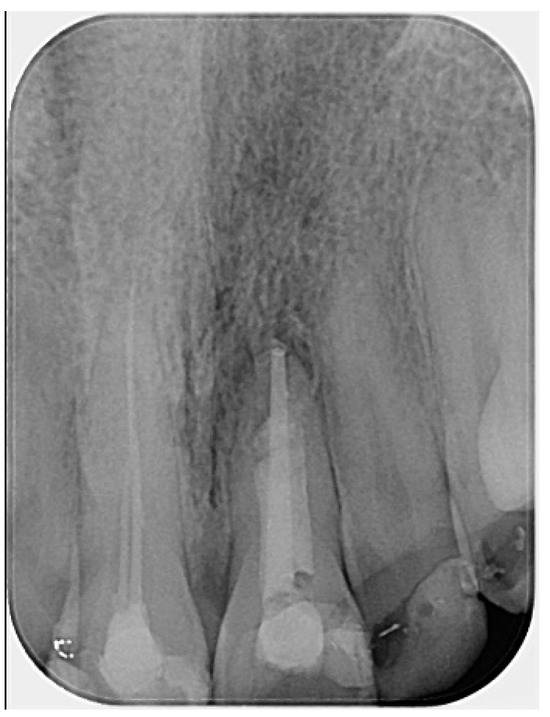

An apical plug was created using calcium silicate-based hydraulic cement (Well-Root PT™ Vericom, Chuncheon-si, Republic of Korea). Prior to placement, the plugger (Buchanan hand pluggers, Kerr Corporation, Orange, CA, USA) was adjusted to be 2 mm short of the working length. A portion of the CSBHC was delivered into the canal, condensed with a plugger, ultrasonically compacted, and then further adapted using a large paper point. After placement, a control radiograph was taken to assess the adaptation of the CSBHC in the apical third. A 4–5 mm apical plug was successfully formed. The rest of the root canal was filled with calcium silicate-based hydraulic cement, which was also condensed with the plugger and ultrasonically compacted, following the concept of primary monoblock (Figure 4).

Figure 4.

Radiograph following root canal obturation with CSBHC. Evidence of bone healing around the apex is visible, likely initiated during the period of calcium hydroxide intracanal dressing. (The mark in the lower left corner indicates the left side).

The radiographs also revealed some imperfections, such as slight inhomogeneity in the root canal filling and a small amount of radiopaque material extruded into the periapical area. This was first observed in the gutta-percha cone trial radiograph (Figure 2), where calcium hydroxide was visible beyond the apex. This is likely attributed to the presence of barium sulfate (BaSO4), a radiopacifier commonly incorporated into commercial calcium hydroxide pastes, which is known to resist resorption when displaced into periapical tissues [32]. Such extrusion can occasionally occur, particularly in cases involving large or chronic periapical lesions, or in teeth with open apices where the natural apical constriction is compromised. The radiopaque material remained visible in subsequent radiographs (Figure 2). It is also possible that the material observed in the later images corresponds to a small extrusion of the calcium silicate-based hydraulic cement used for the apical plug. The presence of this material did not result in any clinical symptoms or adverse effects, nor did it appear to interfere with the periapical healing process, as confirmed by radiographic follow-up. While this finding may be considered as a technical imperfection, it did not compromise the overall favorable outcome of the present case. Nevertheless, such issues should be avoided whenever possible. Although the treatment followed in this case was adapted to patient-specific constraints, and therefore may slightly deviate from standard endodontic protocols, it provides a clinical perspective on the potential for non-surgical healing in cases of apical fenestration.